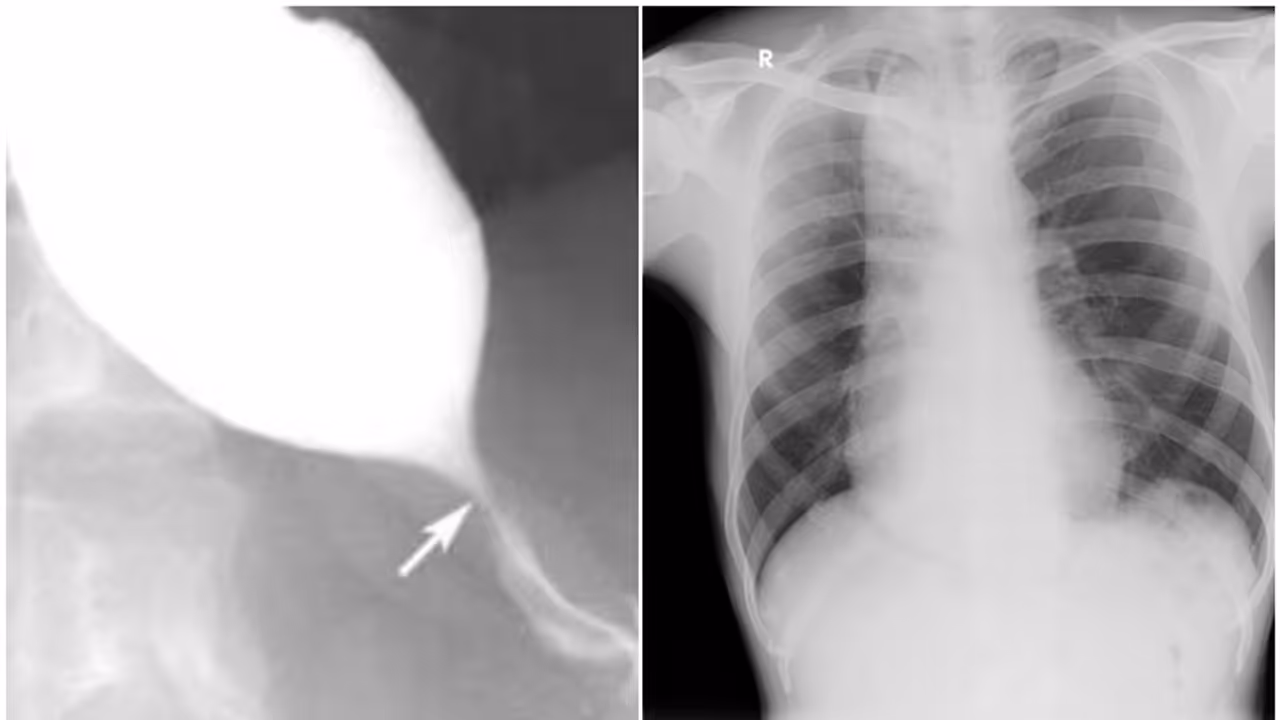

കോഴിക്കോട്: കോഴിക്കോട് സര്ക്കാര് മെഡിക്കല് കോളേജില് അതിനൂതന ചികിത്സ വിജയം. അന്നനാളത്തിന്റെ ചലന ശേഷിക്കുറവ് മൂലം രോഗിയ്ക്ക് ഭക്ഷണം കഴിക്കാന് കഴിയാത്ത അവസ്ഥ ഉണ്ടാക്കുന്ന അക്കാലാസിയ കാര്ഡിയ എന്ന രോഗത്തിനാണ് വിദഗ്ധ ചികിത്സ നല്കി ജീവിതത്തിലേക്ക് തിരികെയെത്തിച്ചത്. ഗ്യാസ്ട്രോ എന്ററോളജി വിഭാഗത്തിന് കീഴിലാണ് എന്ഡോസ്കോപ്പി വഴി നടത്തുന്ന അതിനൂതന ചികിത്സയായ പിഒഇഎം (POEM: Per Oral Endoscopic Myotomy) നല്കിയത്. ചികിത്സയ്ക്ക് ശേഷം രോഗി സുഖം പ്രാപിച്ചു വരുന്നു. നൂതന ചികിത്സ നല്കിയ മെഡിക്കല് കോളേജിലെ മുഴുവന് ടീം അംഗങ്ങളേയും ആരോഗ്യ വകുപ്പ് മന്ത്രി വീണാ ജോര്ജ് അഭിനന്ദിച്ചു.

കാസര്ഗോഡ് സ്വദേശിയായ 43 കാരനാണ് ചികിത്സ നല്കിയത്. വര്ഷങ്ങളായി ഭക്ഷണം ഇറക്കുന്നതിന് തടസം നേരിടുകയും കഴിക്കുന്ന ഭക്ഷണം വായില് തിരികെ തികട്ടി വരികയും ചെയ്തിരുന്നു. മറ്റ് പല ആശുപത്രികളിലും ചികിത്സ തേടിയെങ്കിലും ഫലമുണ്ടായില്ല. തുടര്ന്നാണ് കോഴിക്കോട് മെഡിക്കല് കോളേജ് ആശുപത്രിയിലെത്തിയത്. ഗ്യാസ്ട്രോ എന്ററോളജി വിഭാഗത്തിലെ വിദഗ്ധ പരിശോധനയിലാണ് രോഗത്തിന്റെ സങ്കീര്ണാവസ്ഥ അറിഞ്ഞത്.

തുടര്ന്നാണ് എന്ഡോസ്കോപ്പി വഴി നടത്തുന്ന അതിനൂതന ചികിത്സയായ പിഒഇഎം നല്കിയത്. സ്വകാര്യ ആശുപത്രികളില് ഒന്നര ലക്ഷം രൂപയോളം ചെലവുള്ള ചികിത്സയാണ് സര്ക്കാര് പദ്ധതിയിലൂടെ സൗജന്യമായി നല്കിയത്. കേരളത്തിലെ ഗവണ്മെന്റ് ആശുപത്രികളിലും മെഡിക്കല് കോളേജുകളിലും ആദ്യമായാണ് ഈ രീതിയിലുള്ള ചികിത്സ നടക്കുന്നത്. പ്രിന്സിപ്പല് ഡോ. സജീത് കുമാര് കെജി, സൂപ്രണ്ട് ഡോ. ശ്രീജയന് എം പി എന്നിവരുടെ ഏകോപനത്തില് ഗ്യാസ്ട്രോ എന്ററോളജി വിഭാഗം മേധാവി ഡോ. കെ സുനില് കുമാറിന്റെ നേതൃത്വത്തിലാണ് ചികിത്സ നല്കിയത്.